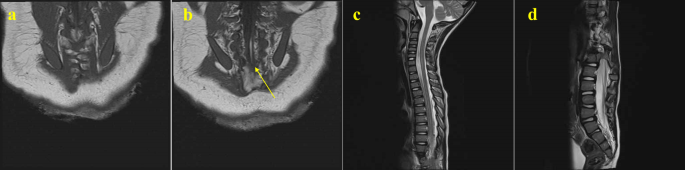

We present two cases with high-level spinal lesions. The first was a boy diagnosed with low-type ARM with an anocutaneous fistula, who underwent posterior sagittal anorectoplasty at three months. Preoperative LāS spine MRI revealed a lipoma in the spinal canal at the S1āS3 level, hemivertebrae at T10 and T11, and spina bifida at the lower sacrum. These findings resulted in a neurogenic bladder and left leg weakness with an unstable gait, requiring an extensive rehabilitation program. No spinal surgery was performed. After three years, due to claudication following long-distance walking, he underwent another MRI series. This whole spine MRI showed a tethered cord with lipoma extending from L4 to the sacral region, hemivertebrae at T10 and T11, and spina bifida consistent with the previous image. Additional findings included hydromyelia or syrinx extending from C5 to the conus medullaris and scoliosis of the TāL spine (Fig.Ā 2). Despite these findings, no surgery was required, and he continued with the rehabilitation program. The second patient, diagnosed with low-type ARM with an anoperineal fistula, underwent surgery at two months of age. Her WS MRI at 11 months showed normal findings in the lumbosacral region but hydromyelia extending over the C2āC7 spinal cord (Fig.Ā 3). She exhibited no neurological symptoms associated with the hydromyelia during outpatient follow-up, and no spinal surgery was performed.

Magnetic resonance imaging (MRI) of a boy diagnosed with low-type anorectal malformation: (a,b) Regional spine MRI at the age of 3 months revealed a lipoma in the spinal canal at the S1āS3 level (arrow) and spina bifida at the lower sacrum. (c,d) Whole spine MRI 3 years later revealed additional findings of hydromyelia or syrinx extending from C5 to the conus medullaris and scoliosis of the TāL spine.